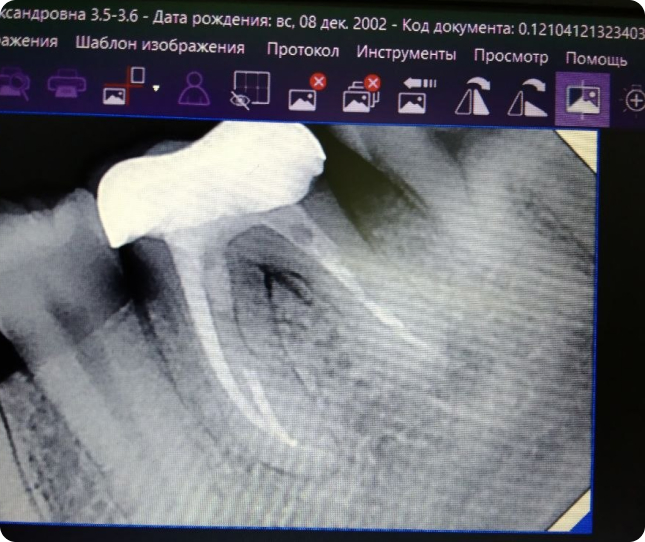

Контроль качества пломбировки каналов

После лечения корневых каналов (эндодонтического лечения) рентгеновский снимок является обязательным. Он позволяет убедиться, что канал запломбирован полноценно и герметично на всю длину, без пустот и выходов пломбировочного материала за пределы корня. Это критически важно для долгосрочного здоровья зуба.